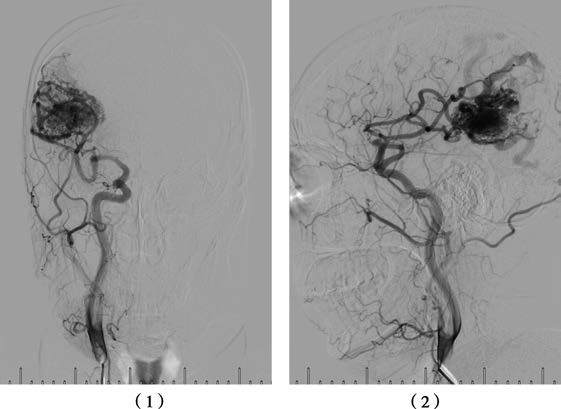

Cerebral Angiography

Cerebral angiography provides details on the size, extent, feeding arteries, draining veins, and flow velocity of the AVM.

Figure 1 Right common carotid artery DSA

(1) Anteroposterior view showing a right parieto-occipital AVM.

(2) Lateral view showing a right parieto-occipital AVM.